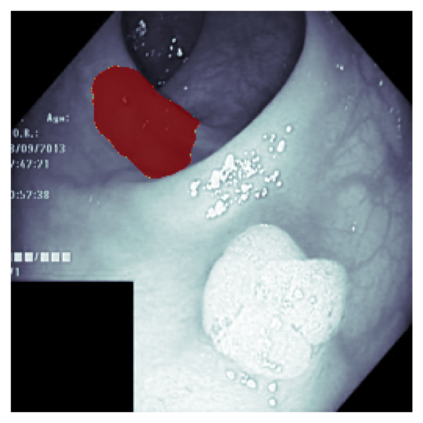

The sigmoid activation is the standard output activation function in binary classification and segmentation with neural networks. Still, there exist a variety of other potential output activation functions, which may lead to improved results in medical image segmentation. In this work, we consider how the asymptotic behavior of different output activation and loss functions affects the prediction probabilities and the corresponding segmentation errors. For cross entropy, we show that a faster rate of change of the activation function correlates with better predictions, while a slower rate of change can improve the calibration of probabilities. For dice loss, we found that the arctangent activation function is superior to the sigmoid function. Furthermore, we provide a test space for arbitrary output activation functions in the area of medical image segmentation. We tested seven activation functions in combination with three loss functions on four different medical image segmentation tasks to provide a classification of which function is best suited in this application scenario.